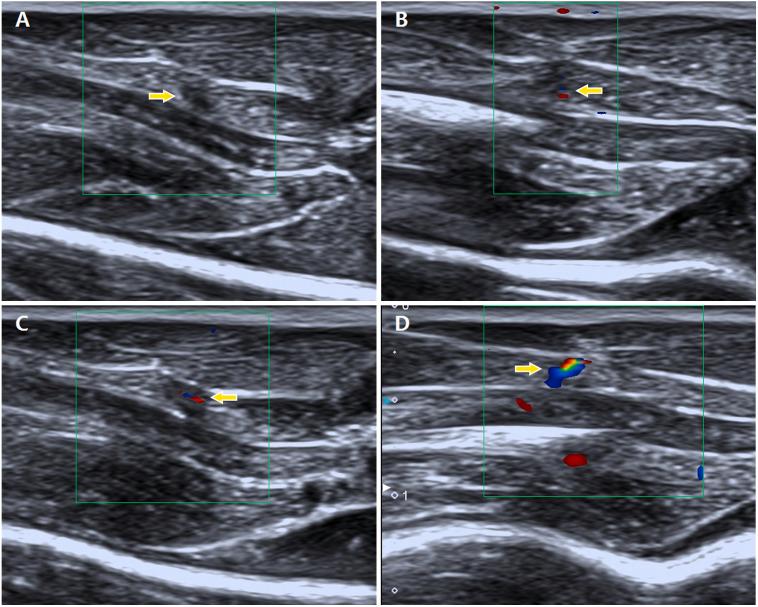

Twenty-five Sprague-Dawley rats were randomly divided into a model group and a normal control group. A model of active MTrPs was established by a blunt strike combined with eccentric exercise. Enzyme-linked immunosorbent assays (ELISAs) were employed to detect the levels of HIF-1 and VEGF. Microvessel density (MVD) was evaluated using immunohistochemistry. CDFI was applied to observe the blood flow signals in the MTrPs, which were classified into four grades based on their strengths.

Compared with the control group, the active MTrP group exhibited significantly higher HIF-1 and VEGF levels and MVD values. These differences were accompanied by increased blood flow signals. In the active MTrP group, the blood flow signal grade was positively correlated with the MVD ( < 0.05) and independently correlated with the VEGF level ( < 0.05) but was not correlated with the expression of HIF-1 ( > 0.05).

Ischaemic/hypoxic conditions may be involved in the formation of MTrPs. CDFI is useful for detection of the features of angiogenesis in or surrounding MTrPs via assessment of blood flow signals.